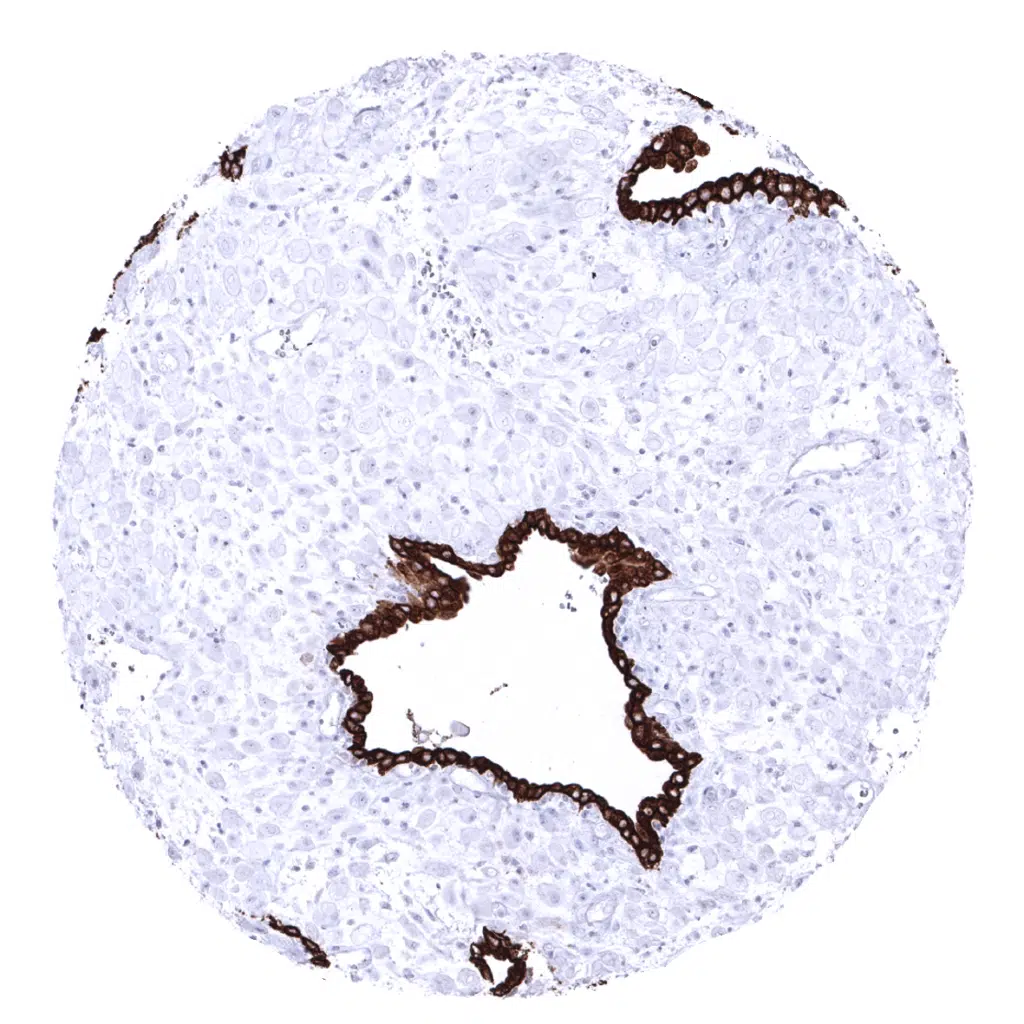

Pancreas - In the pancreas, the intensity of pan Cytokeratin immunostaining decreases from intercalated and excretory ducts to acinar cells and is even lower in islet cells.